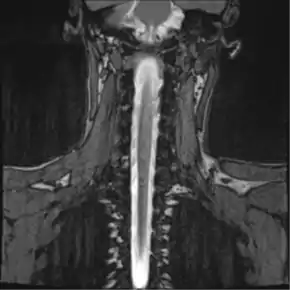

![]() Thoracic MR Myelogram |

Magnetic resonance myelography (MR myelography or MRI myelography) is a noninvasive medical imaging technique that can provide anatomic information about the subarachnoid space. It a is type of MRI examination that uses a contrast medium and magnetic resonance imaging scanner to detect pathology of the spinal cord, including the location of a spinal cord injury, cysts, tumors and other abnormalities. The procedure involved the injection of a gadolinium based contrast media into the cervical or lumbar spine, followed by the MRI scan.[1][2]

The radiologist will first numb the skin with the local anesthetic and then inject the gadolinium based contrast media into the spinal cord at the interspace between third and fourth lumbar vertebrae (L3-L4). Then the patient will be asked to roll on the table until the contrast is evenly distributed in the spinal cord and fill the nerve roots. Then the patient will be transferred to the MRI table and the scan will be taken.